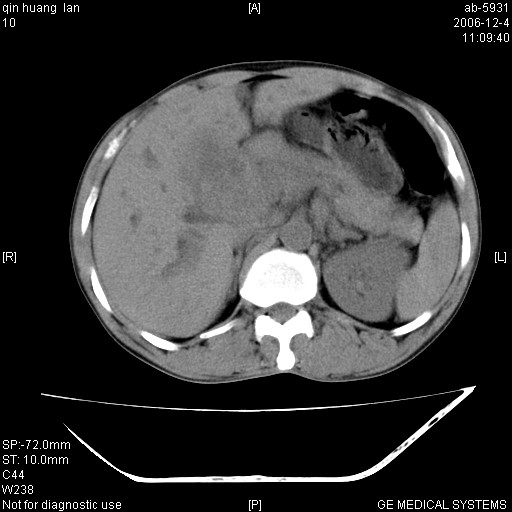

以下是引用qiuleiyu在2006-12-4 19:07:00的发言:[br]1、无基础肝硬化表现。[br]2、左右肝内胆管明显软藤样扩张。[br]3、肝门区肿块,呈现延时花瓣样强化。而非快进快出强化。[br]4、胰头大,然密度较均,未见双管征。[br]5、后腹膜多发淋巴肿大。[br]考虑肝门部胆管ca伴胰头及后腹膜广泛淋巴转移及胆总管扩张。必要时mrcp进一步检查。

以下是引用jinguoji在2006-12-5 13:08:00的发言:[br][br]肝门区胆管细胞癌 并肝门、胰头周围、腹后淋巴结肿大转移。